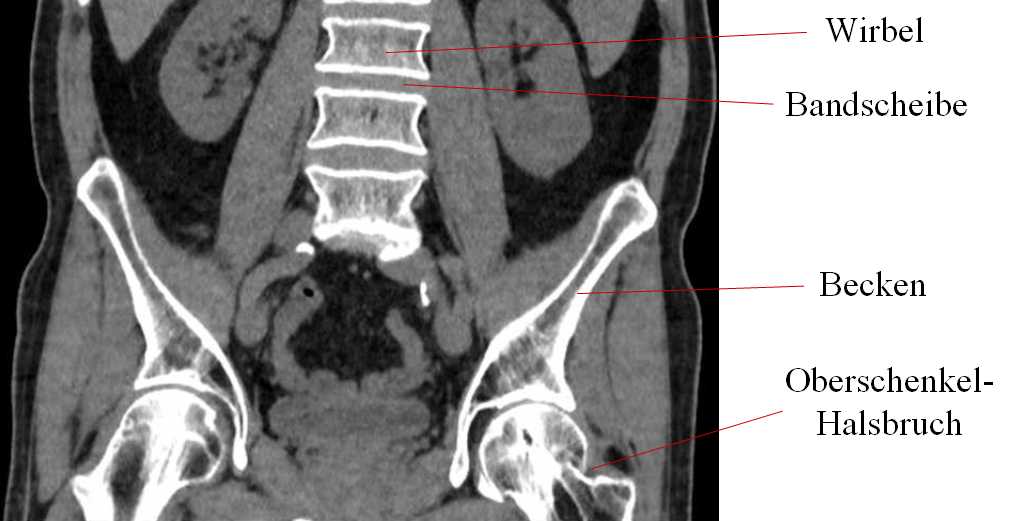

Abb.1: Ausschnitt aus einer Computer-Tomographie (CT). Man erkennt den verheilten Oberschenkel-Halsbruch, sowie Wirbel und Bandscheiben.